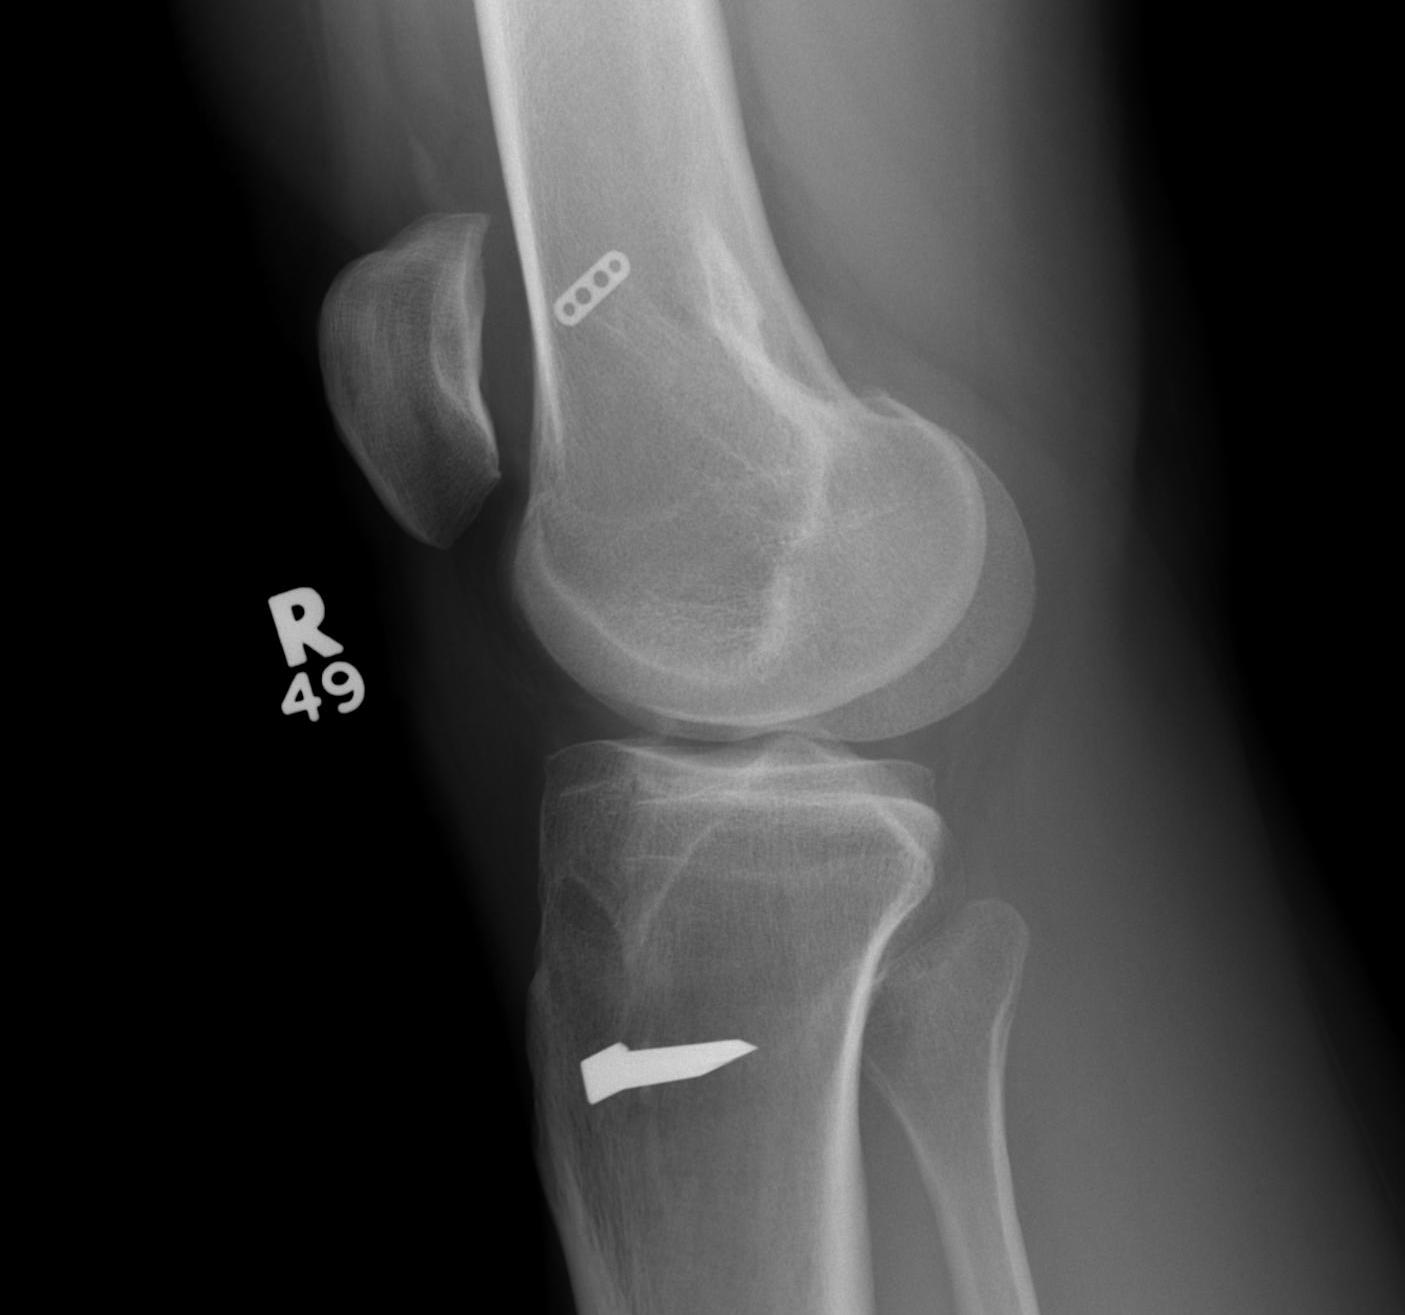

Case 1

Patient with traumatic failure ACL, previous hamstring with endobutton and bioabsorbable screw

Graft likely too vertical, evidence of tibial tunnel lysis

Old staple had to be removed. Graft passed and fixed on femoral side with 9 x 25 mm screw.

Achilles tendon fixed on tibial side with 9 x 25 screw

Tibial bone very poor and screw little bite (advanced very easily too far into tibia, but not seen in joint).

New staple used, but had to be repositioned as cortical bone soft and fracture easily.